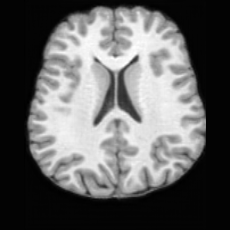

(a)PathologicalInput ImageSynthSR [18]Brain-ID [28]UNA [30]USBHealthyGround TruthRefer to captionRefer to captionRefer to captionRefer to captionRefer to captionRefer to captionRefer to captionRefer to captionRefer to captionRefer to captionRefer to captionRefer to captionRefer to captionRefer to captionRefer to captionRefer to captionRefer to captionRefer to captionRefer to captionRefer to captionRefer to captionRefer to captionRefer to captionRefer to caption(b)HealthyInput ImageConditionalLesion MaskUNA [30]USBRefer to captionRefer to captionRefer to captionRefer to captionRefer to captionRefer to captionRefer to captionRefer to captionRefer to captionRefer to captionRefer to captionRefer to captionRefer to captionRefer to captionRefer to captionRefer to caption

Figure 5: Comparison of bidirectional brain editing. (a) pathology-to-healthy, the circles and arrows highlight lesion regions and unsuccessful reconstructions; (b) healthy-to-pathology. Note that SynthSR and Brain-ID cannot perform healthy-to-pathology editing.

Pathology-to-Healthy Editing. Fig. 5 (a) presents comparison results on four input brain images with lesions of varying sizes, shapes, and densities. All competing models, although specialized for healthy brain image synthesis, struggle to reconstruct pathological regions, especially near lesion boundaries. In contrast, USB accurately reconstructs the corresponding healthy brain, even in challenging cases with large, high-density lesions where normal brain structures are almost completely obscured (last row). Tab. 2 provides a quantitative comparison for pathology-to-healthy editing, where USB achieves the best performance across all three datasets, demonstrating the effectiveness of its unified framework in reconstructing healthy brains from pathological inputs. Additional results are in Suppl. B.

Healthy-to-Pathology Editing. As shown in Fig. 5 (b), given a healthy brain image paired with a random lesion mask, USB seamlessly embeds the lesion into the healthy anatomy, producing realistic pathological appearances consistent with surrounding structural context. Yet UNA’s syntheses are visually unrealistic, with the conditioned lesion mask simply overlaid as a parallel layer onto the healthy brain. Tab. 3 further demonstrates USB’s superior performance. The evaluation was conducted on 100 pairs of lesion masks and healthy brains, with real stroke images